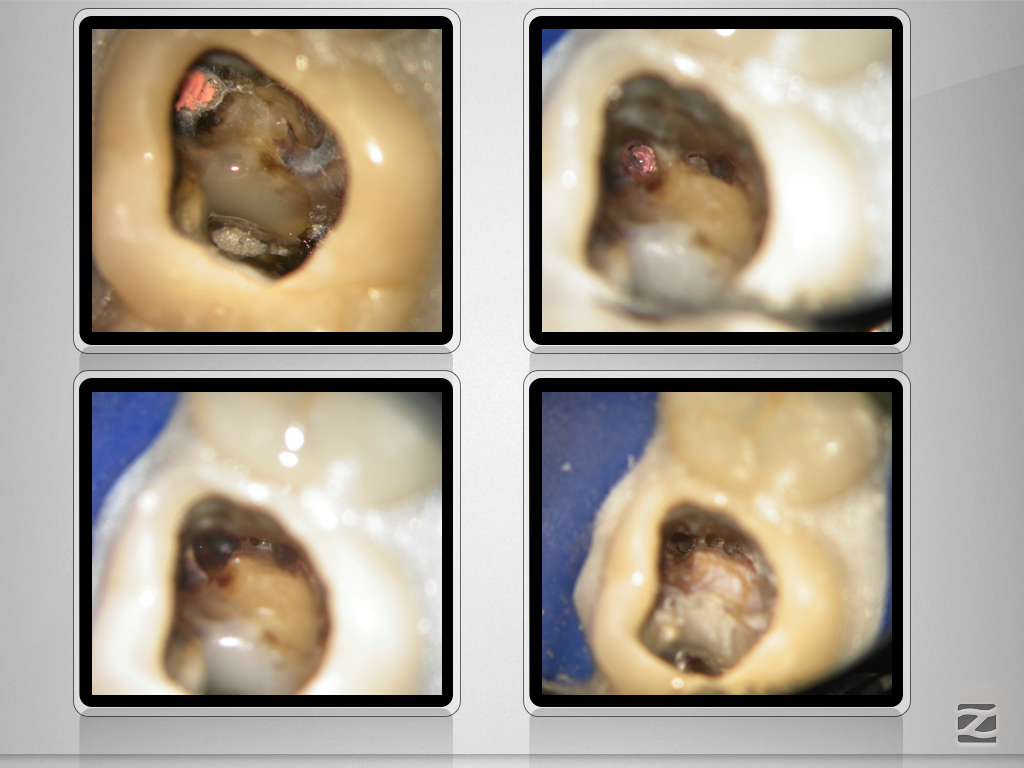

2526d-008

Enter Sandman